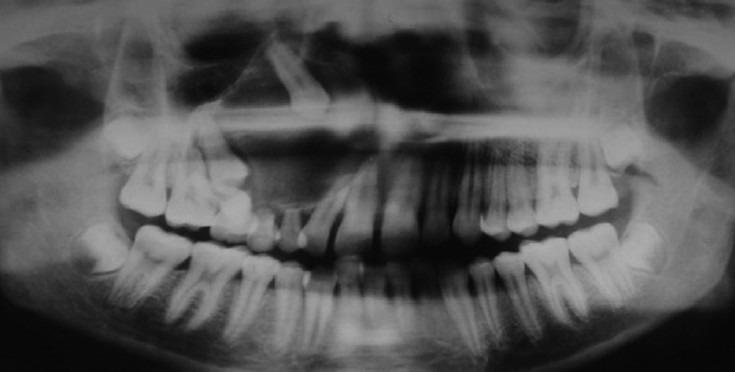

Hemangiomatous ameloblastoma (HA), which is a rare ameloblastic variant, is presented in a 15-year-old boy in the maxillary right molar region associated with unerupted canine and premolars. Radiologic and computed tomographic analysis was suggestive of cystic lesion. An histology picture confirmed the diagnosis of HA. There are less than eight cases documented in the literature and mostly are in the middle age with mandibular location. This is first ever reported case of HA in a 15-year-old boy with maxillary location. Due to less number of documented cases and no long-term follow-ups, clinical behavior and prognosis of this lesion are uncertain. In this case report, the clinical, histological, and radiographic features of HA are presented.

血管瘤样成釉细胞瘤(HA)是一种罕见的成釉细胞变异型,发生于一名15岁男孩的右上颌磨牙区,与未萌出的尖牙和前磨牙相关。放射学和计算机断层扫描分析提示为囊性病变。组织学图像确诊为HA。文献记载的病例少于8例,大多数发生于中年,位于下颌骨。这是首次报道的发生于15岁上颌骨的HA病例。由于记录在案的病例数量较少且缺乏长期随访,该病变的临床行为和预后尚不确定。本病例报告展示了HA的临床、组织学和影像学特征。